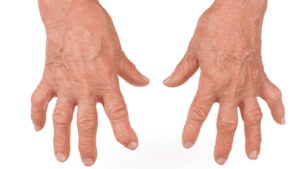

Join us in exploring the multifaceted realm of hand pain. Discover its origins, from overuse to underlying health conditions, and learn about effective remedies and preventive strategies. Our articles cover the impact of repetitive tasks, ergonomic solutions, and therapeutic exercises to alleviate discomfort.

Common Conditions of the Hand